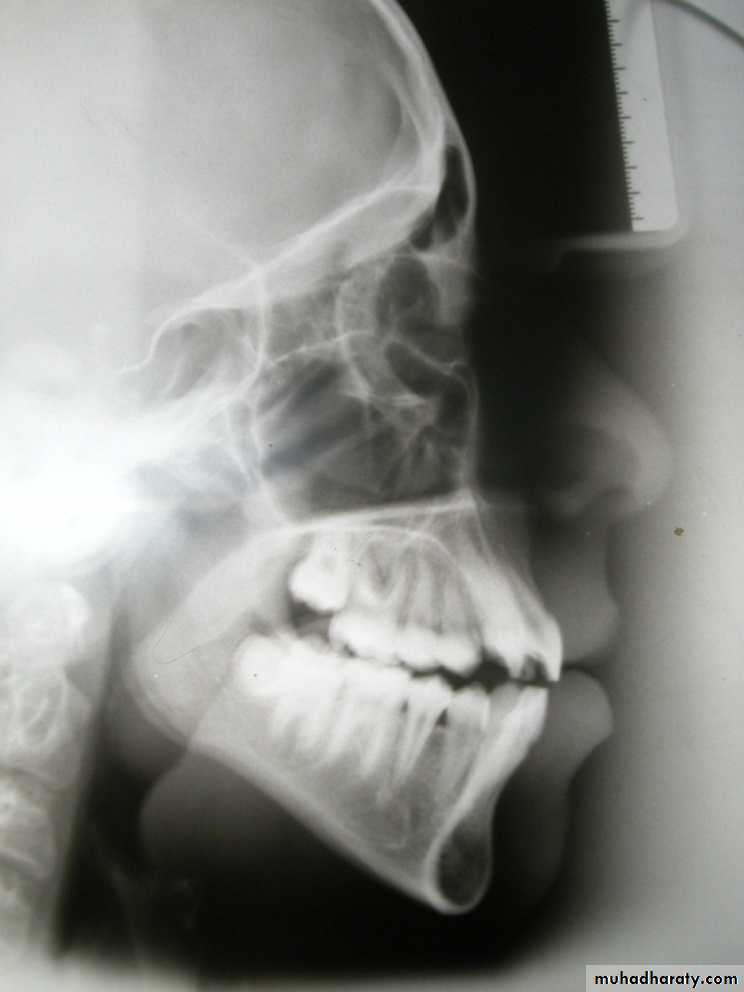

Antero-posterior skeletal relations

N-S-Gn (Y-Axis) = 66⁰This angle determine the position of the mandible relative to the cranial base

N

S

Gn

Vertical skeletal relations

MM angle (27 + 5)Large angle = Skeletal open bite

Normal angle = NormalSmall angle = Skeletal deep bite

Frankfort-mandibular angle (27 + 5)Large angle = Skeletal open bite

Frankfort-SN angle (6 + 5)32

Vertical Skeletal Assessment

Skeletal Vertical AssessmentNS(SN plane)-GoGn